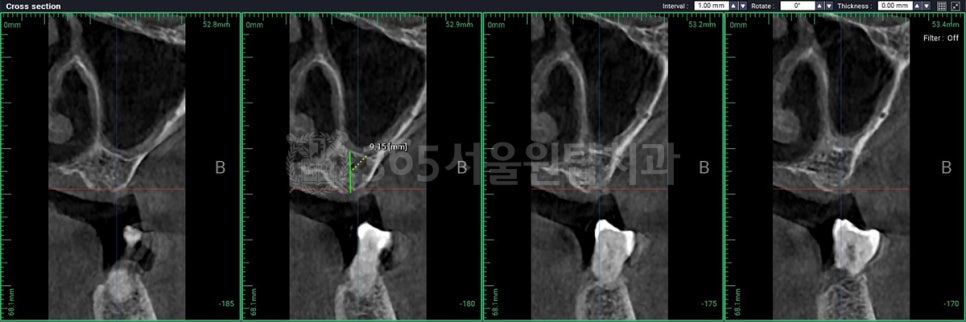

강서구 임플란트 365서울원탑치과의 CT 예시자료입니다.

3차원 CT를 통한 정밀 진단,

치조골의 밀도와 형태 분석,

전신질환을 고려한 치료 계획까지